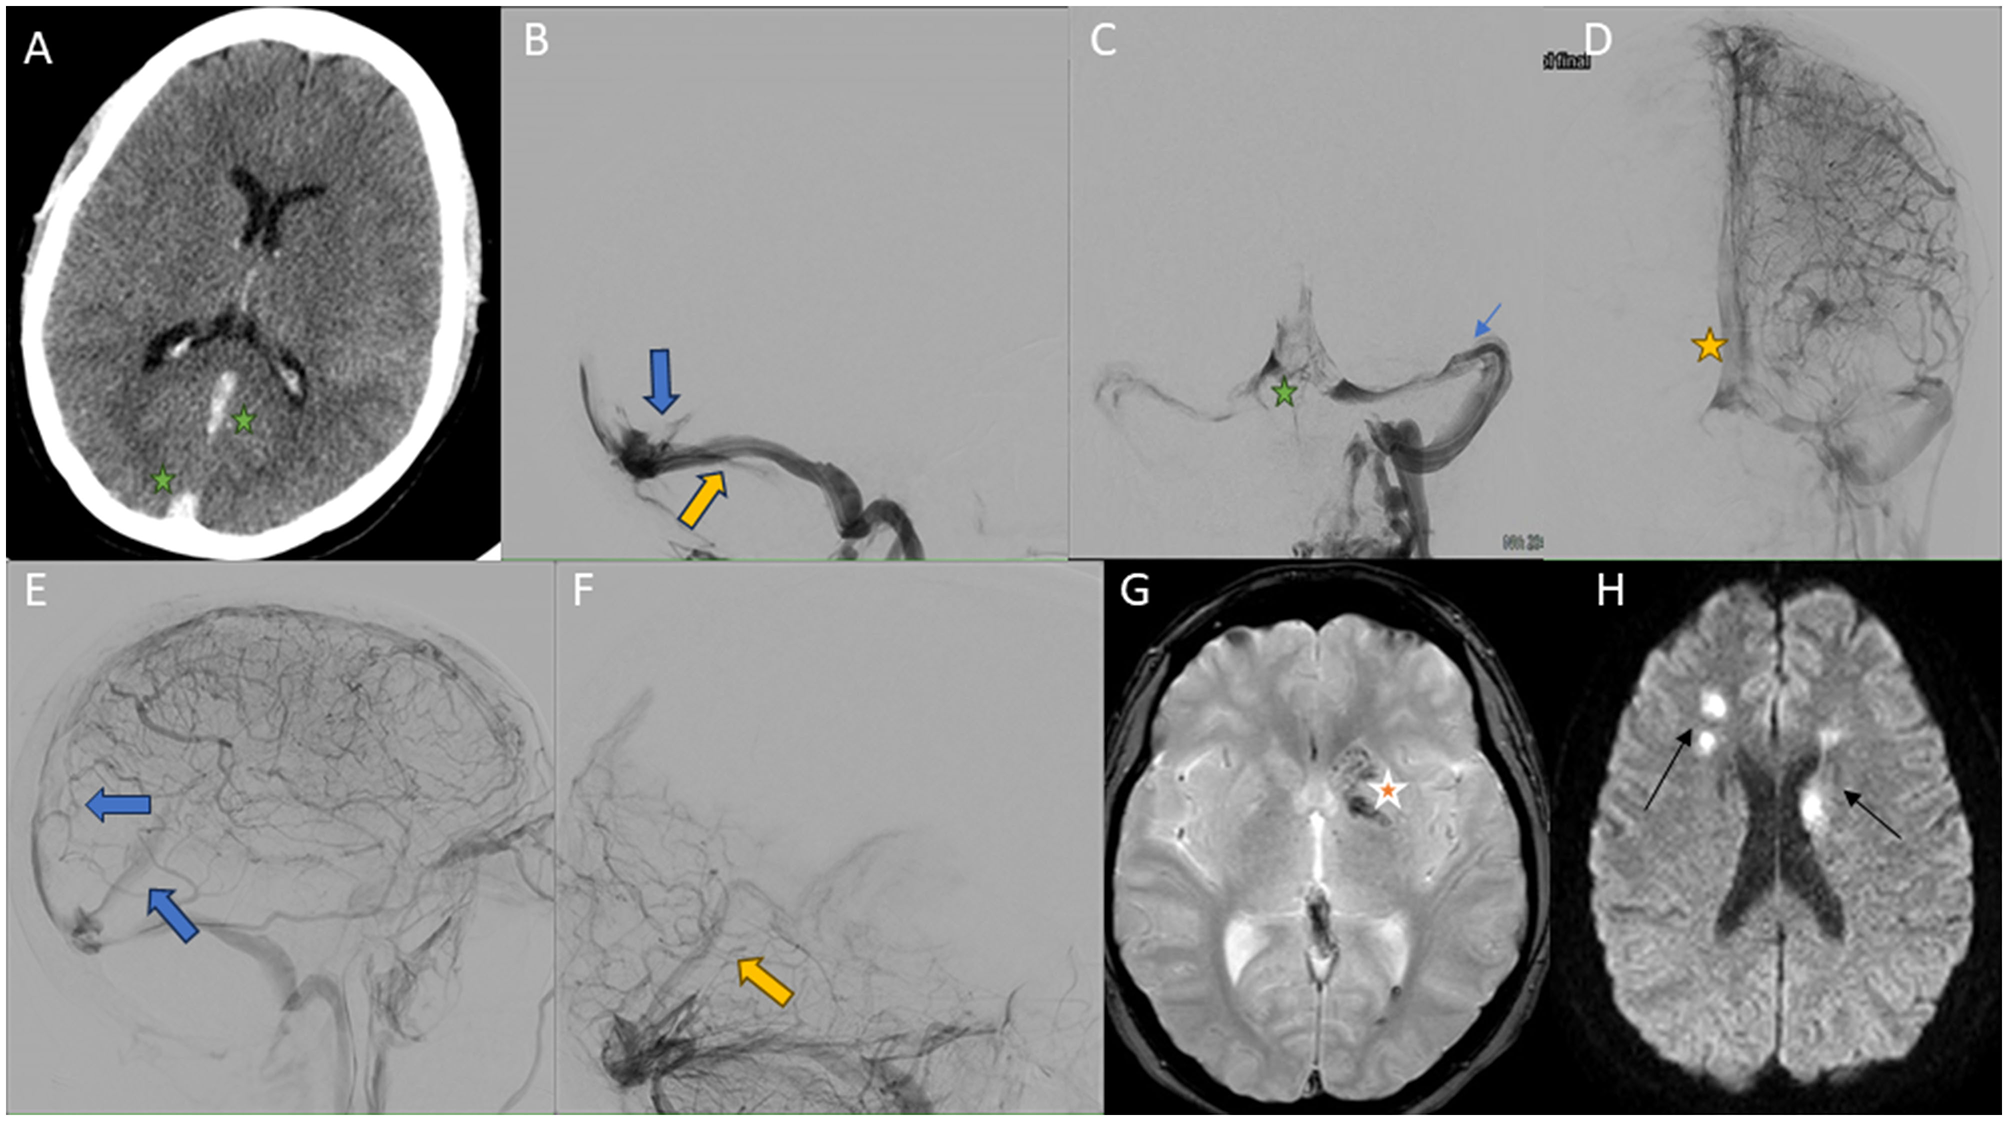

Figure 2. Images obtained during the course of case 1. (A) Cerebral CT scan without intravenous contrast. CVT with hyperdensity of superior sagittal sinuses (green star), rectus sinus (green star), vein of Galen, and internal cerebral veins. (B) Cerebral venography obtained by left internal jugular access, lateral view. An extensive thrombus with involvement of the rectus sinus is visualized (blue arrow). Direct aspiration was performed with the Neuron MAX 0.88® device (yellow arrow), followed by access to the rectal sinus with a microcatheter and TigerXL® device (not shown in the image). (C) Cerebral venography obtained by left internal jugular access, anteroposterior view. Recanalization of left transverse-sigmoid sinuses (green star) is evident after manual and pump aspiration through Neuron MAX 0.88® and JET7®. Guide catheter is can be seen in these sinuses (blue arrow). (D, E) Selective left internal carotid arteriography cerebral arteriography in venous phase, anteroposterior (D, E) view. Repermeabilization of the previously occluded sinuses can be seen (superior sagittal sinus [yellow star in (D) and blue arrow in (E)], rectus sinus and deep cerebral veins [blue arrow in (E)]), with residual partial thrombosis persisting at the torcula. (F) Selective left vertebral arteriography lateral view. Recovery of deep venous drainage (yellow arrow). (G, H) Brain MRI, susceptibility-weighted (G) and diffusion weighted images (H). Multiple signal alterations with diffusion restriction affecting bilateral basal ganglia, right thalamus and supratentorial white matter, compatible with venous infarcts (black arrows) with hemorrhagic transformation (red star).

The study was completed with cerebral arteriography, which showed large CVT with involvement of the sagittal and transverse sinuses and torcula, as well as involvement of the deep venous system (Figure 2B). MT was performed with manual and pump aspiration with Neuron MAX 0.88® and JET7® devices, as well as with a stent retriever (Trevo® 6 mm). A 4F diagnostic catheter was placed in the vertebral artery for successive diagnostic series. Cerebral venous circulation was accessed by puncture of the left internal jugular vein, placing a guide catheter in the sigmoid sinus and the beginning of the transverse sinus. Successive aspirative MT were performed on the left transverse dural sinus, right transverse sinus, superior sagittal sinus and with stent retriever in the rectus sinus (total passes: 6), removing large amount of clot. Final controls showed recovery of the deep venous drainage (Figures 2C–F). At 24 h, the patient demonstrated complete neurological recovery. A control TCD study was performed, which showed reduced pulsatility and venous flow indices corresponding to deep venous system turbulence (vein of Rosenthal), which may it be suggestive of partial recanalization. Cerebral MRI was completed and revealed a patchy venous infarction with hemorrhagic transformation (Figures 2G, H). She was discharged with discontinuation of oral contraception, treatment with folic acid 5 mg/24 h and anticoagulation with acenocumarol (vitamin K inhibitor). The modified Rankin Scale was 0 at discharge and at 3 months.